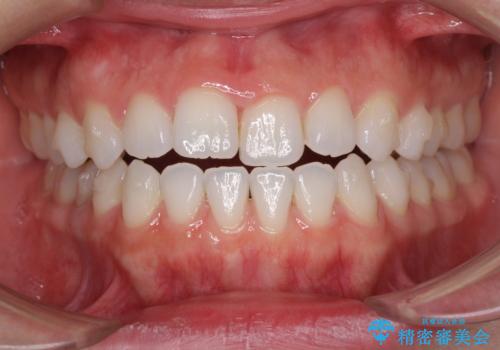

反対咬合を治したい インビザラインによる矯正治療

- 上下の前歯の反対咬合を気にして来院された患者様です。

インビザラインを用い、下顎はIPR(歯と歯の間を削る)と歯列全体を後方に移動させ、上顎は前歯を持ち上げることで、反対咬合を改善していくこととしました。

インビザラインによる反対咬合の改善は、上の歯が下の歯を乗り越えていく期間に咬み合わせが非常に不安定となり、治療が長期化することがあります。

こちらの患者様も、一時的に前歯でしか咬めない時期がありましたが、比較的早く咬み合わせが安定し、1年ほどで治療を終えることができました。